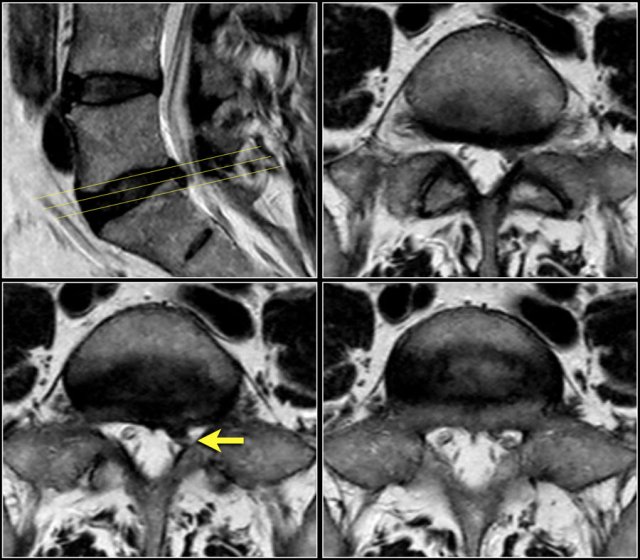

Here we have the axial images of the same patient.

Notice the dumbbell configuration of the synovial cyst at the level of the neuroforamen (yellow arrows).

Synovial cysts can be easily overlooked.

On these T2W-images it looks as if the foramen is normal.

Notice that the nerve is missing.

In fact the neuroforamen is almost completely filled by the synovial cyst, which compresses the nerve root against the vertebra (arrows).

The nerve can hardly be seen.